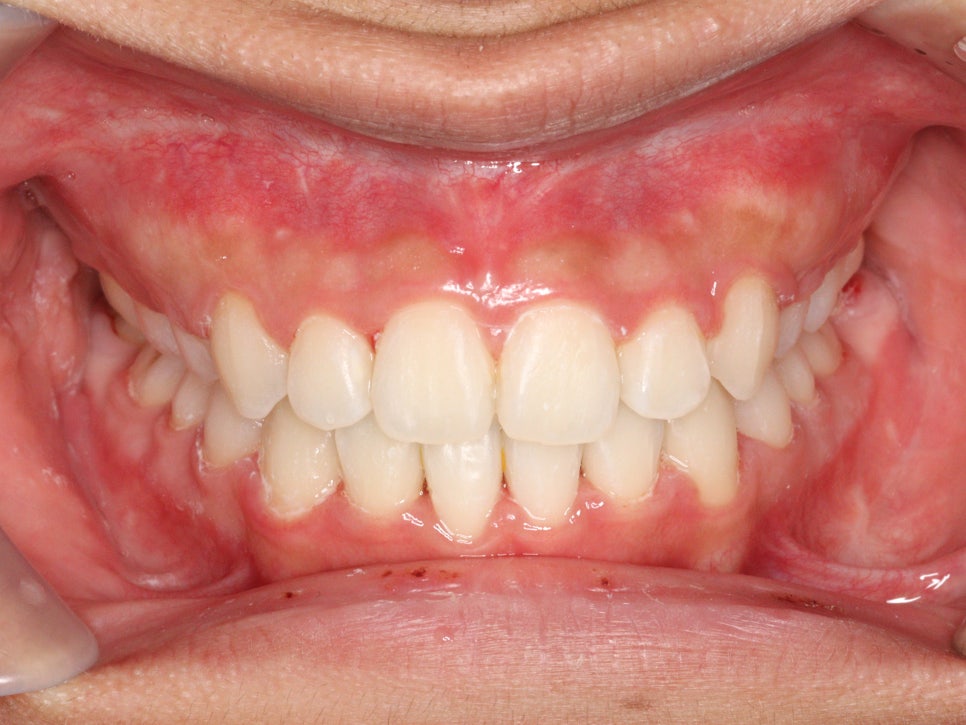

최근에 오셨을때 모습입니다.

아쉽게도 처음 끝날때와는 약간은 다른 중심선을 관찰하였습니다.

하지만 좌우 교합은 긴밀하게 유지되고 있었고 안모의 변화 등 다른 부작용은 관찰되지 않았습니다.

환자분의 전, 중간, 후 의 입안과 얼굴모습을 시리즈로 한번 보고 마무리 하겠습니다.